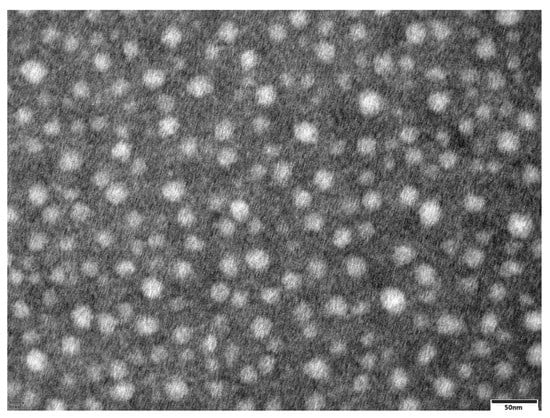

3.3. TEM

TEM images of the optimized formulation demonstrated that the morphology of the phytosomes exhibited a well distributed spherical particle shape, as shown in Figure 1. The TEM results demonstrated that the diameters of the DG-P were approximately 20 nm.

Figure 1.

TEM photographs of DG phytosomes (×40,000).